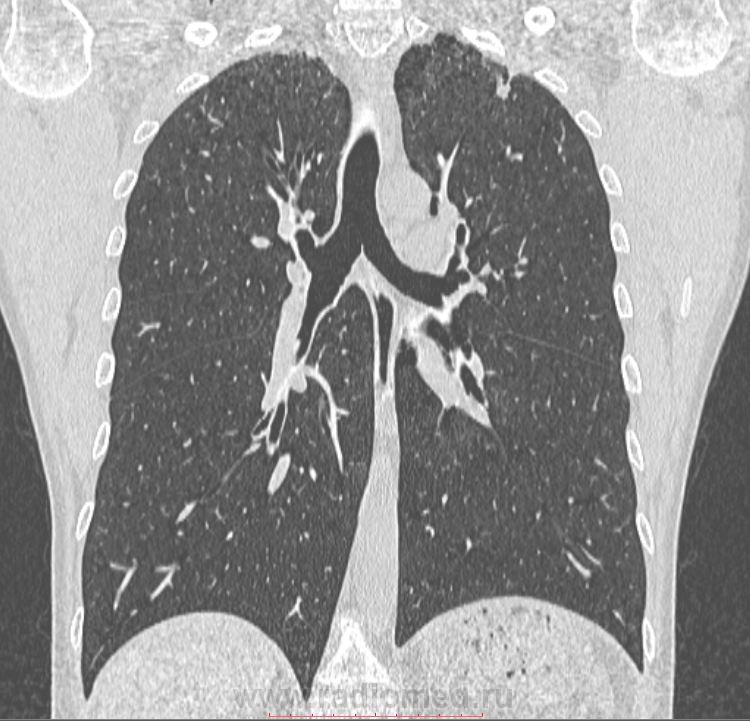

Фотографии и снимки КТ легких без контрастных веществ